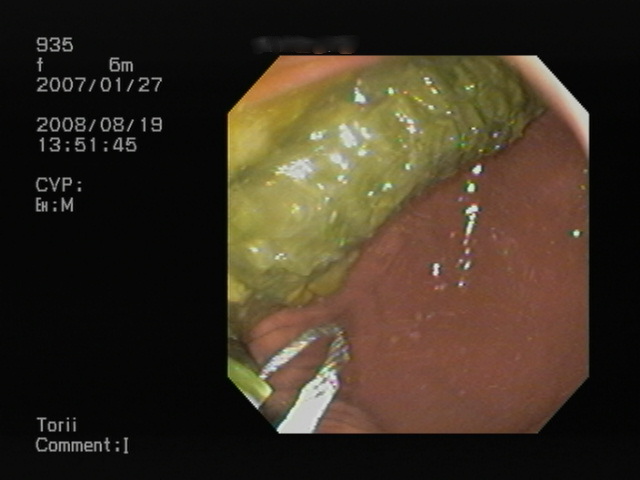

内視鏡画像です。

胃の中に大きく移ったその物体は・・・

と〜もろこしの芯です。

意外にも炭化せずにそのままの状態でした。(胆汁色で緑がかってはいますが)

かなり大型のものだったので、内視鏡で使用出来る摘出鉗子が使用出来ませんでした。

大きくて掴めないんです。

よって自作のスネアーを使用し、それで摘出しました。

時間がかかりましたが、なんとか2つのもろこしの芯を摘出いたしました。